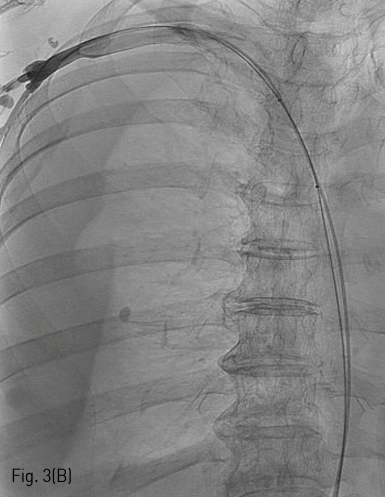

국소 마취를 시행하고 우측 대퇴정맥을 천자하여 0.035 인치 유도 철사 (Terumo, Tokyo, Japan) 와 5F C2 catheter (Cook, Bloomington, IN) 를 이용하여 catheter를 우측 쇄골하정맥에 위치시키고 시행한 정맥조영술에서 상대정맥의 협착을 확인하였다 (Fig. 1). 0.035 인치 유도철사를 따라 직경 10mm, 길이 4cm sized balloon catheter (ATB advance; Cook, Bloomington, IN) 를 삽입하여 상대정맥의 협착부위에 대해 풍선 확장술을 시행하였다 (Fig. 2). 10mm balloon으로 확장 중 waist가 발생하였으며 6 atm 시 waist가 소실되었다 (nominal pressure 5 atm, burst pressure 14 atm). 풍선 확장술 시행 후 시행한 정맥조영술에서 상대정맥에 조영제 유출과 우측 폐에 혈흉이 관찰되었다 (Fig. 3A, B). 이에 즉시 0.035 인치 유도철사를 따라 직경 10mm balloon catheter를 다시 삽입하여 조영제 유출 부위에 대해 balloon tamponade를 시행하였다. Balloon tamponade 후 시행한 정맥 조영술에서 조영제 유출의 양은 감소하였으나 지속적인 조영제 유출이 관찰되어 0.035 인치 유도철사를 따라 직경 14mm, 길이 6cm sized Wallstent (Boston scientific, Natric, MA)를 조영제 유출 부위에 설치하였다. 시술 후 시행한 정맥조영술에서 스텐트를 통한 혈류의 흐름이 원활하고 더 이상 조영제 유출이 되지 않는 것을 확인하였다 (Fig. 4). 혈흉의 치료를 위해 10.2F drainage catheter (Cook) 를 우측 흉강에 설치하였다.

Fig 3B

(B) A radiograph demonstrates hemothorax in the right pleural space.